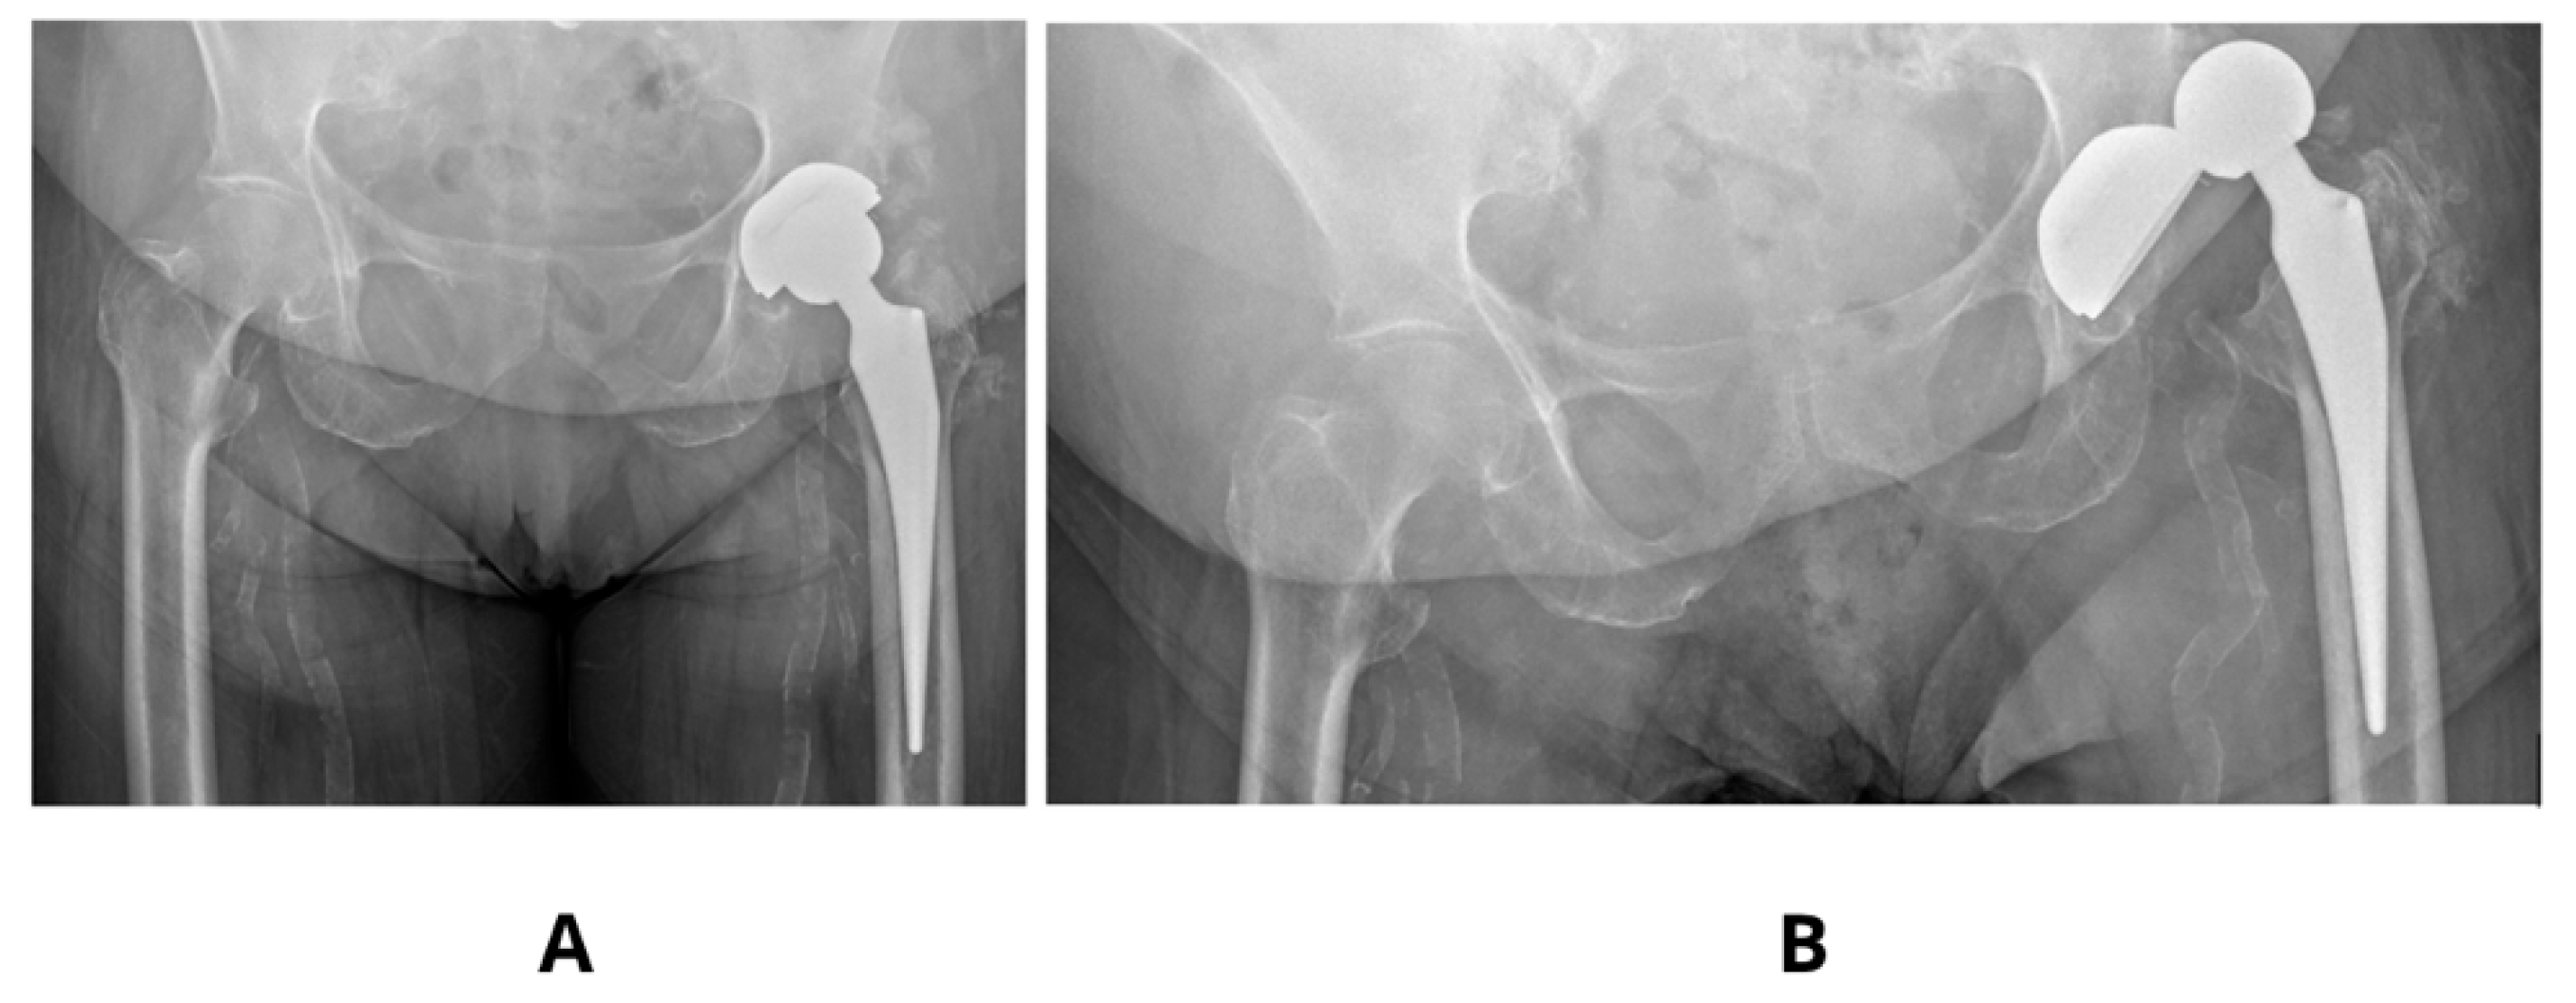

Figure 4. Clinical case showing an acetabulum with increased anteversion and inclination angle 60°—(A,B). Dislocation of the same prosthesis—(C).

Literature examples emphasizes that precise acetabular positioning within the so-called functional safe zone is essential for minimizing biomechanical complications. According to Teja et al. [17] even minor deviations outside the 30–50° inclination and 5–25° anteversion range can impair prosthesis biomechanics and compromise functional stability. Observed in our studies decrease in SF to values as low as 2–3 in models with increased anteversion (30°) and shallow stem insertion highlights the sensitivity of these parameters and aligns with clinical findings, finding its confirmation in our clinical observations [Figure 4].